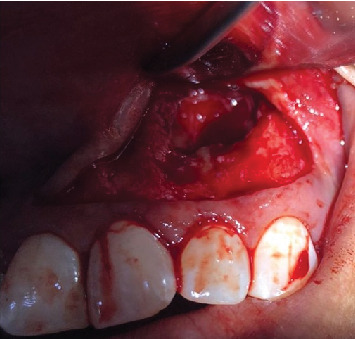

The radicular cyst is an inflammatory pathology affecting the periapical bone tissue associated with teeth exhibiting pulp necrosis. Without timely endodontic intervention, this pathology can lead to significant bone tissue destruction due to its growth pattern, necessitating both endodontic and surgical approaches to halt its progression and remove the involved tissue. This case study details the management of a 23-year-old patient with a history of prior trauma, presenting with pressure in the anterior maxillary region. Tomographic examination revealed a hypodense area involving Teeth 2.1, 2.2, and 2.3. A surgical approach involving enucleation and endodontic treatment was undertaken. The diagnosis was confirmed histopathologically, and follow-up radiographs demonstrated satisfactory bone filling.

根性囊肿是一种影响根尖周围骨组织的炎症性病理,伴有牙髓坏死。如果不及时进行牙髓治疗,由于其生长模式,这种病理会导致严重的骨组织破坏,需要牙髓治疗和手术方法来阻止其进展并切除相关组织。本病例研究详细介绍了一名23岁的患者的治疗方法,该患者有外伤史,表现为上颌前区压力。断层扫描显示低密度区,包括牙齿2.1、2.2和2.3。手术方法包括去核和根管治疗。组织病理学证实诊断,随访x线片显示满意的骨填充。